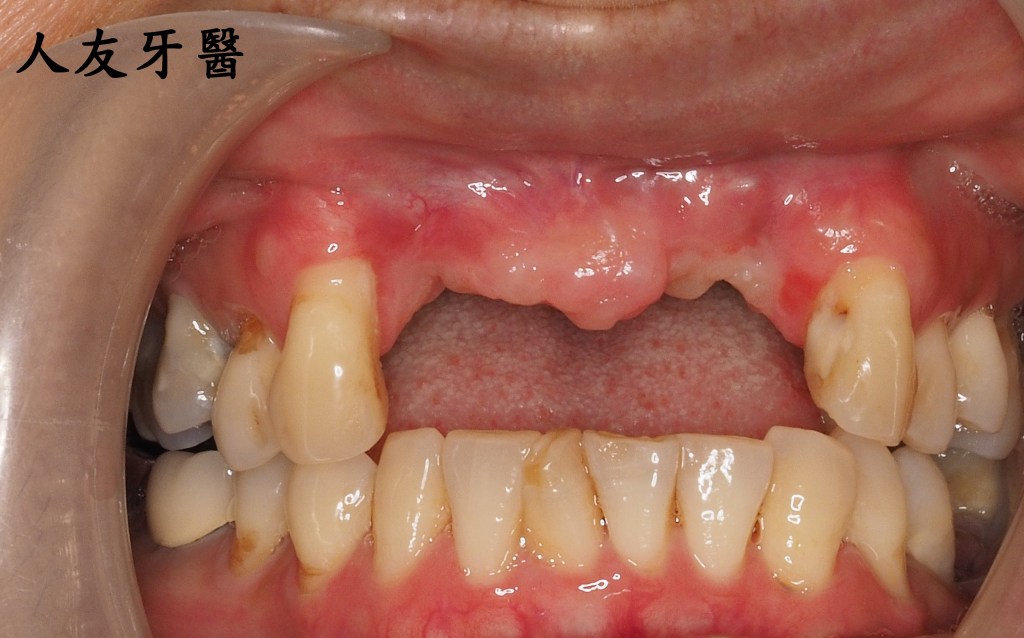

這位年輕女性患者的門牙和側門牙在別家治療半年,也有做四顆相連的牙橋,一直覺得很不舒服,笑起來不自然也不美觀,聽到鑽牙齒的聲音也很害怕。

下圖是別家做的牙橋

想詢問周醫師如何處理。醫師看了X-RAY發現右邊側門牙紅色圓圈的地方有病變,有可能留不住。左邊側門牙藍色箭頭牙齒有裂到肉,也可能留不住。經過討論後建議都拔除。